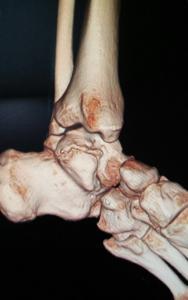

Tarsal koalisyon, ayak kemiklerinin gelişimi sırasında oluşan bir ayrışma anomalisidir. Bu kemikler arasındaki birleşme fibröz doku, kıkırdak veya kemikten oluşmuş olabilir. Toplum içerisindeki görülme sıklığı %1 oranında bildirilmektedir ve olguların yarısında diğer ayakta da tarsal koalisyona rastlanır. En sık; talokalkaneal ve kalkaneonaviküler eklemler arasında koalisyon görülür.

Öykü ve fizik muayene yol gösterici olmakla birlikte ayak AP-Lateral ve oblik grafileri tanı açısından yardımcı olmaktadır. Doktorunuz cerrahi planlanmasında veya tanı açısından şüphe duyulması durumunda ise bilgisayarlı tomografi ve manyetik rezonans tetkiki ile detaylı inceleme yapmak isteyebilir.